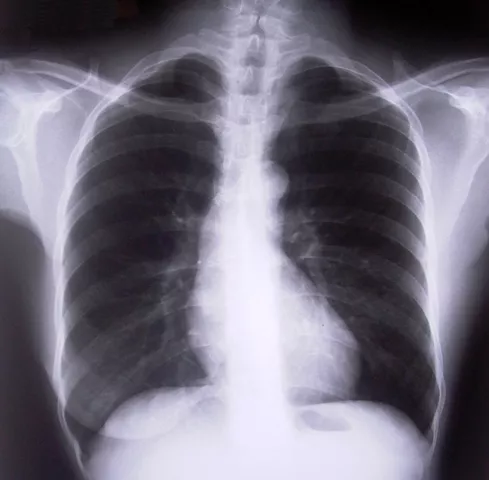

Pneumococcal disease is caused by a bacterium called streptococcus pneumonia, also known as pneumococcus. Diseases caused by pneumococcus include pneumonia, meningitis and bacteraemia—the presence of bacteria in the blood.